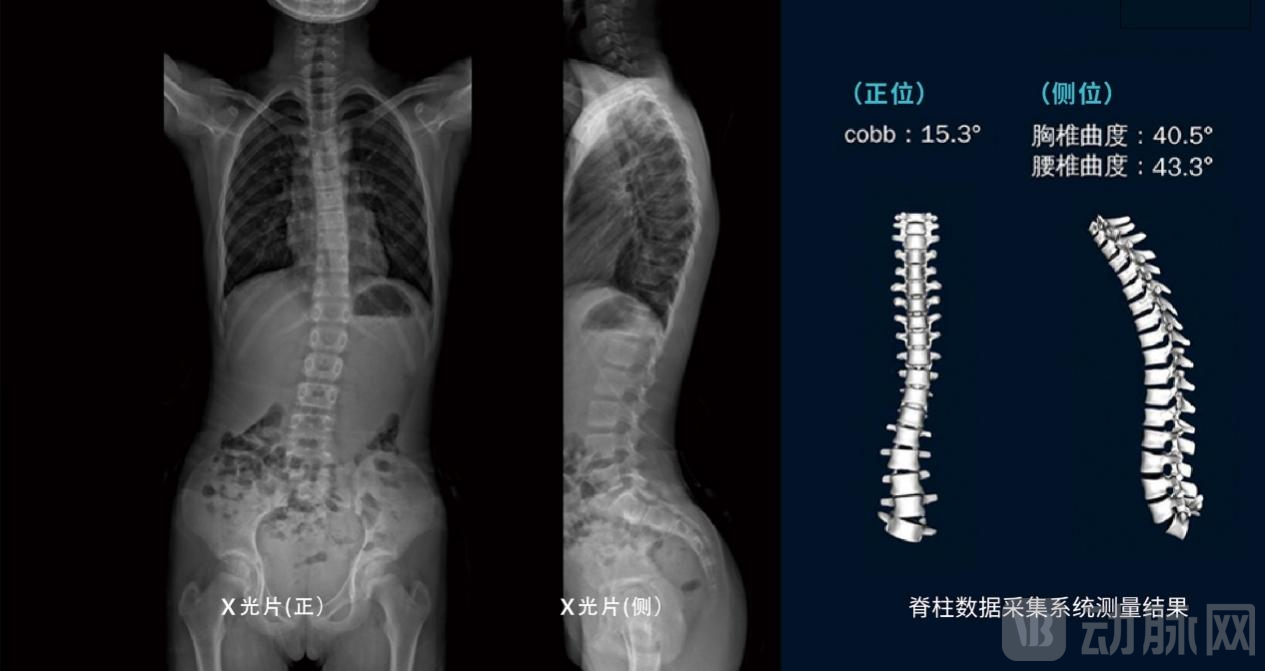

本次FDA审批通过的“脊柱三维测量仪”便是一种具有高灵敏度、准确度、安全性的新型筛查方法,为全球首款无辐射直接测量脊柱Cobb角和ATR角的脊柱健康检查设备。在上海瑞金医院放射科完成的双盲临床验证试验中(与国际最先进的脊柱侧弯X线影像设备EOS对比),已有初步测量结果显示,该设备在脊柱侧弯检测方面与X光有显著一致性。

该产品集智能光感技术、地形扫描技术、多传感器信息融合技术于一身,辅以增益控制技术、数字孪生技术,以及数字化映射的技术,可无辐射获取3D脊柱报告图(数据信息包括Cobb角、胸椎曲度、腰椎曲度、ATR角度等),实现对脊柱的三维仿生镜像呈现。有效解决传统脊柱侧弯诊断过程中,因医生测量技术水平参差不齐导致的检测结果假阳性率高、结果可重复性差,检测辐射面积较大等痛点。